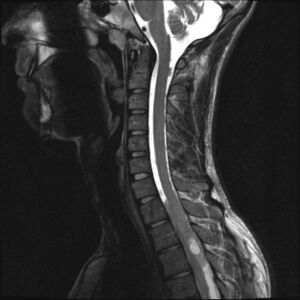

- MR – primary choice, especially axial and sagittal T1 and T2 images. In practice, DTI (diffusion tensor imaging) and FT (fiber tractography) are already commonly used for more detailed imaging of white matter pathways (their displacements, compression, etc.) due to tumor location. [5][6][7].

- Diagnostika: DTI, MRI